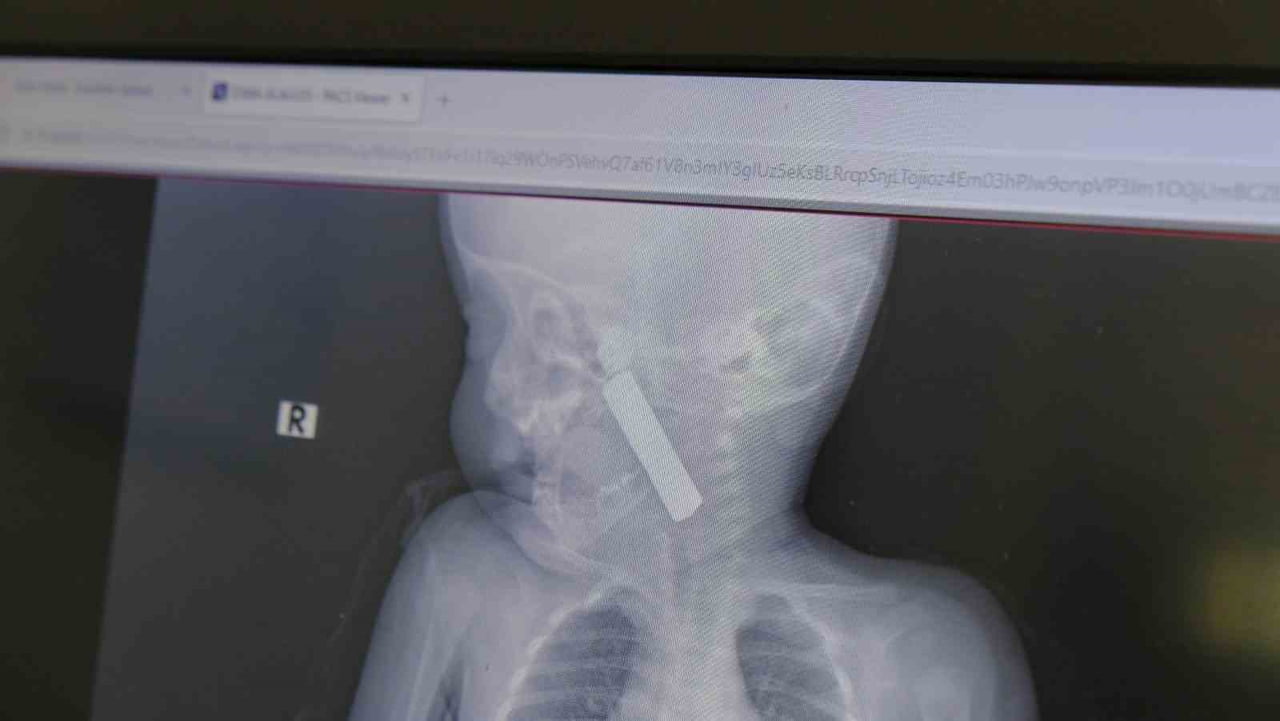

Karaman Eğitim ve Araştırma Hastanesi acil servisine kusma şikayetiyle getirilen 6 aylık E.A. isimli kız bebekte yapılan muayene ve tetkiklerde, boğazına kumanda pili kaçtığı tespit edildi.

Bebekte solunum sıkıntısı gözlenirken hastanın oksijen satürasyonu yaklaşık 90 civarındaydı ve siyanotik görünüm mevcuttu. Durumun ciddiyeti üzerine bebek vakit kaybetmeden ameliyata alındı.

Çocuk Cerrahisi Uzmanı Doç. Dr. Mehmet Uysal başkanlığındaki ekip tarafından yapılan operasyonda, anestezi ekiplerinin entübasyonunu takiben laringoskop ve magill forseps kullanılarak yabancı cisim çıkarıldı.

Doç. Dr. Mehmet Uysal olayla ilgili, "Acil polikliniğimize kusma şikayeti ile 6 aylık bir kız bebek getirilmiş ve bize haber verildi. Biz de vakit kaybetmeden geldik, hastamızı gördük. Yapılan tetkikler sonucunda, ağız tabanına oturan ve yemek borusunun birinci darlığına kadar uzanan, kumanda pili dediğimiz bir pille karşılaştık. Filmde ve muayenede bunu gördük. Hastayı ilk gördüğümüzde bayağı siyanotik durumda, solunum sıkıntılıydı ve oksijen satürasyonu 90 civarındaydı. Böyle olunca bir an önce beklemeden hızlı bir şekilde ameliyathaneye götürdük. Orada ameliyathanedeki anestezi uzmanlarımız ve personel bize yardımcı oldu, hasta hızlı bir şekilde entübe edildi. Ondan sonra da laringoskop ve magill forseps dediğimiz malzemelerimizle bu yabancı cismi çıkarmış olduk. Bir an evvel müdahale ettik, iyi ki müdahale ettik, orada ağız tabanında, özellikle ön kısmında hasar oluşmuştu. Müdahale sonrasında da hastanın solunum problemleri bir süre devam etti, bu yüzden 24 saat takip ettik. Herhangi bir problem oluşmayınca 24 saat sonra kontrole gelmek üzere hastayı taburcu ettik," dedi.